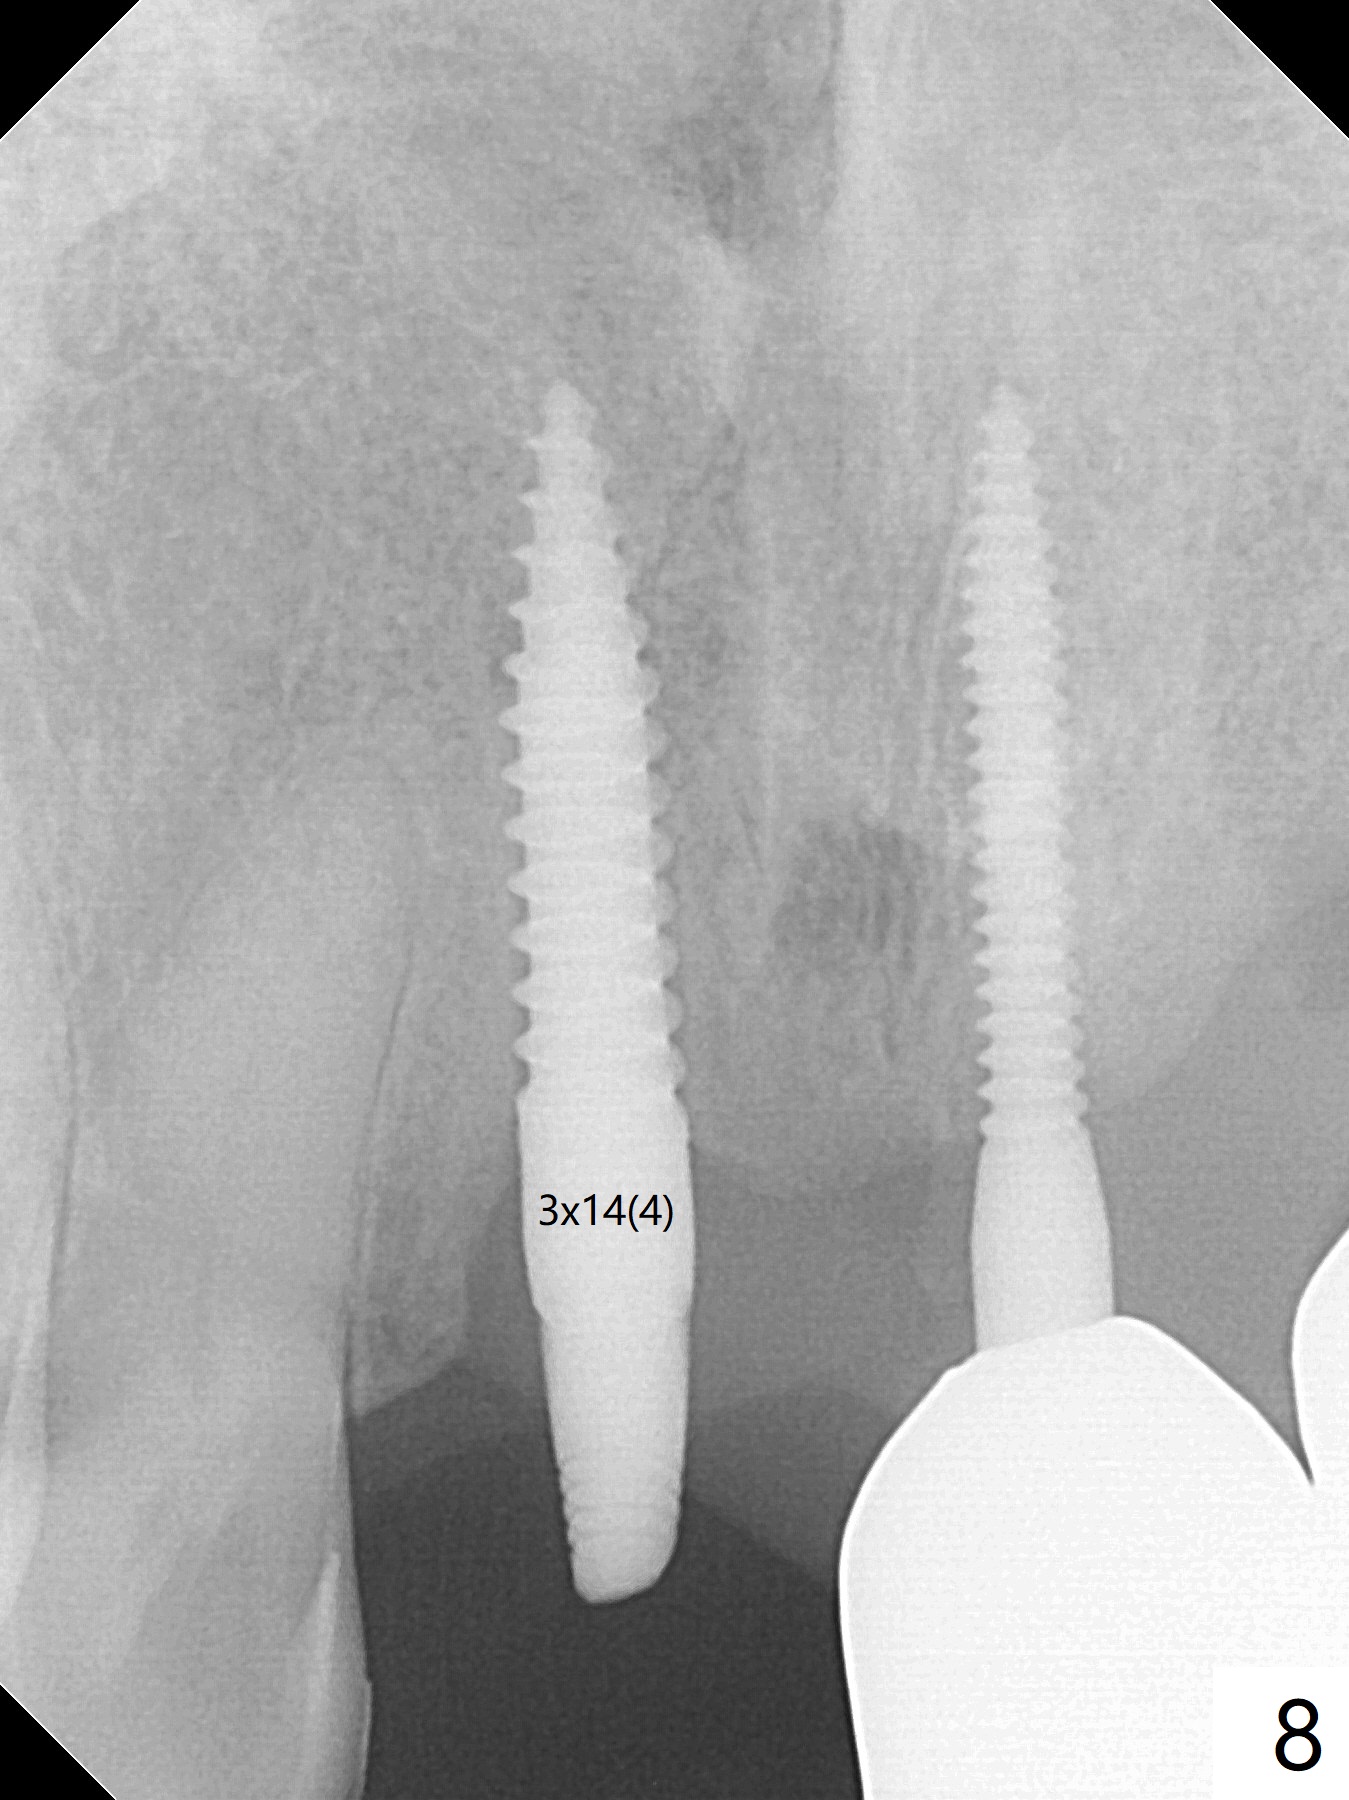

A 43-year-old man has 6 of 1-piece implants in the maxilla (#8-13). His daughter's head hits his upper anterior teeth 7 months post cementation. Exam shows that the tooth #7 has mild percussion. Nine months later the implant crown at #8 becomes displaced and loose when he bites apple (Fig.1 arrow). Forceps are used to remove the crown, leaving a concave implant site (Fig.2). After the crown is bonded to the neighboring tooth/implant crown (Fig.3 *), the patient feels pain from the neighboring tooth. The alveolus is 4.3 mm wide (Fig.4 (2.9 mm preop)), allowing 2.5 or 3.0 mm immediate implant re-placement (Fig.5). A 2.0/3.0 mm trephine bur will be used for implant removal. Try to place the new implant slightly distal to improve the trajectory (Fig.6). Particulate and/or onlay graft is an option. Prepare dummy implants. As planned, the fractured implant is removed by using a 2.0/3.0 mm trephine bur following incision (Fig.7). After use of Lindamann bur to remove the distal bone, a 3x14(4) mm dummy implant is placed with 20 Ncm (Fig.8). A longer implant could be used (3x16(2 or 4) mm), but a 3.5x13 mm 1-piece implant is placed with ~ 50 Ncm after use 3.0 mm drill (Fig.9,10). Allograft is placed around the implant (Fig.9,10 *), followed by Amnion-Chorion membrane and 5-0 PGA sutures (Fig.11). Allograft placed around the implant (Fig.9 *) appears to be able to prevent implant thread exposure 4 months postop (Fig.12). PA is taken when the crown is cemented (Fig.13). Four months postop cementation of #8 crown, the patient returns because of #9 mobility (Fig.14). In fact the implant fractures when the loose crown is removed with forceps; there is bone loss at #10. Bone graft will be placed at #10 with sticky bone (PRFx1), while the implant at #9 is redo. The ridge is wide enough for a 3.5x10 mm implant (Fig.16 (CT taken when #8 implant fractured)). Also prepare Tatum angled 1-piece implant. The 2 mm implant is too thin when occlusion contact at #10-13 is incomplete. The crowns will be redone when the implant at #9 is osteointegrated.